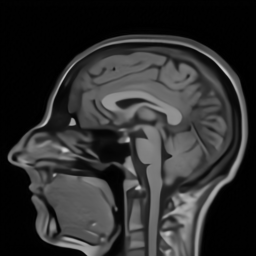

| Ground Truth (PSNR) | Zero-filling (22.33) | TV (25.22) | SIDWT (25.10) | PBDW (27.39) | |

| PANO (28.77) | FDLCP (29.78) | ADMM-Net (27.91) | BM3D-MRI (29.35) | Ours (30.48) |

First, we test on 25 T1-weighted MRI data using three different undersampling patterns with a fixed 10% sampling rate. Fig. 3 shows the quantitative results (PSNR). Our method performances best for all three cases and has stronger stability compared with the second best method on variance. As for the effect of sampling ratios variation, we use radial mask under 10%, 30% and 50% sampling rates with evaluation of RLNE and MSE. Fig. 4 shows that our method has the lowest reconstruction error for all sampling rates. For more intuitive comparison, we illustrate the reconstruction error in term of pixels in Fig. 5. We also offer the qualitative comparison in Fig. 6. Visualized results demonstrate our method has better performance in both artifacts removing and details restoration. Time consuming is also considered. We compare our method with others on the 25 T1-weighted data using Radial mask with 10% and 50% sampling rate. Notice that ADMM-Net and ours are tested on GPU for the incorporation of deep architecture. Tab. 1 shows that our method provides an efficient reconstruction process and comes to the fastest method among the state-of-the-art competitors.